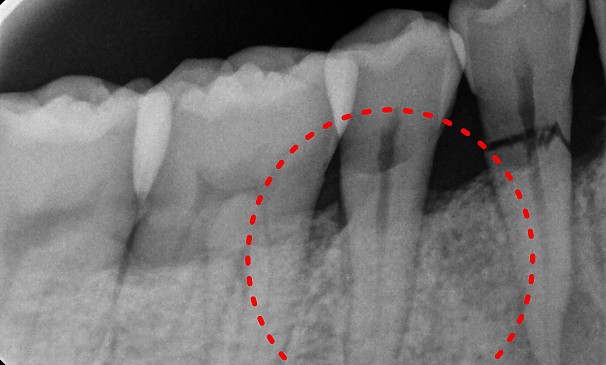

기존의 일반 신경치료의 경우 재료의 특성상 완전한 밀폐가 쉽지 않아 치료한 부분에서 세균이 다시 자랄 수 있으나 특수 신경치료(MTA)는 밀폐, 방수효과가 뛰어나 세균이 자라날 공간이 없어 미세신경관이 많거나 신경관이 기형적으로 생겨 있는 등 어렵고 난이도가 높은 신경치료가 필요할 때 시술하게 됩니다.

치료 전